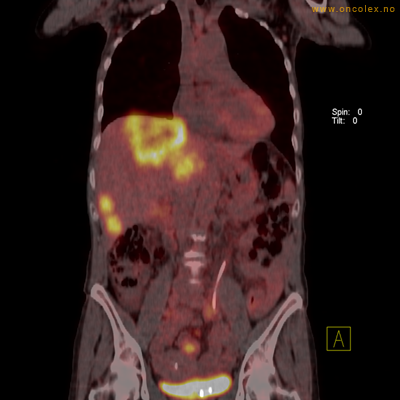

PET/CT (PET: Positron Emisjons Tomografi/ CT: Computer Tomografi) er en avansert nukleærmedisinsk bildetakingsmetode. Metoden er et godt dokumentert, veletablert og svært nyttig verktøy i bildediagnostikk ved kreft. Et PET-kamera gir tredimensjonale bilder av hele kroppen. Integrert CT gjør at informasjonen fra PET blir lokalisert anatomisk nøyaktig.

Kort beskrivelse av undersøkelsen

Gjennom en nål (plastkanyle) i en blodåre i armen vil du få et radioaktivt stoff. Det mest vanlige er radioaktivt druesukker (18F-FDG). Stråling fra det radioaktive stoffet registreres i PET-skanneren og viser hvordan dette stoffet fordeler seg i kroppen. Det normale opptaket av det radioaktive stoffet vil være endret ved sykdomsprosesser. Celler med høyt stoffskite, som for eksempel kreftceller, har økt opptak av sukker. Ved undersøkelsen kan man dermed ofte se større opptak av det radioaktive sporstoffet i kreftsvulster.  Siden CT tas samtidig, kan PET og CT bildene legges sammen og vise nøyaktig hvor i kroppen det økte opptaket er.

Eksempler på funn

Vev som tar opp mer radioaktivt stoff, synes som hvite områder som lyser opp mer i forhold til annet vev som tar opp mindre sukker.